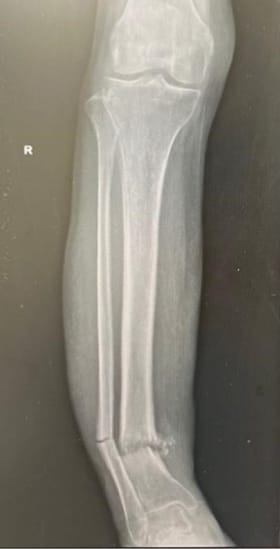

El estudio corresponde a un reporte de caso clínico, en el que se describe a una paciente femenina de 85 años con diagnóstico de osteomielitis tuberculosa primaria en la tibia derecha, causada por Mycobacterium tuberculosis.

Clínicamente, la paciente presentaba una lesión crónica en la extremidad inferior derecha, caracterizada por una herida de larga evolución sin cicatrización, acompañada de deformidad angular en varo.

Tras radiografías y tomografías de la extremidad inferior derecha, se observó una fractura transversal completa de la tibia y peroné distal, infección piogénica y sospecha de formación de abscesos.

Tras la intervención quirúrgica, la paciente continuó con un régimen antituberculoso sistémico por nueve meses como parte del tratamiento. El estudio confirma una alineación postoperatoria favorable y una reintegración de movimiento progresiva.

Al año del retiro del fijador externo, las heridas habían cicatrizado, las imágenes de estudio demostraban una correcta unión de la fractura de la tibia y la paciente podía desplazarse de manera independiente.